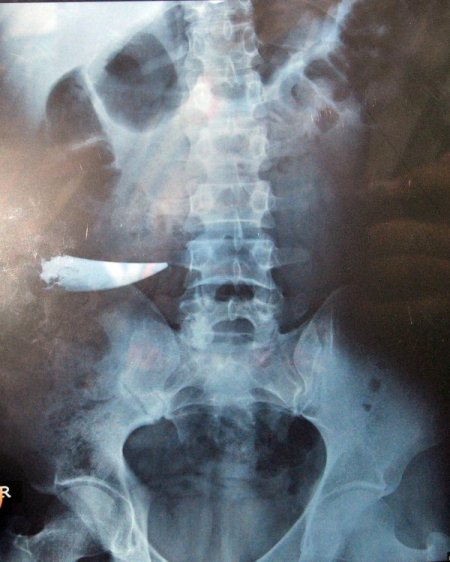

Nihat Çevik 2003 yılında bir köy düğünde çıkan tartışmada karnından bıçaklandı. Kan kaybı nedeniyle kendinden geçen Çevik, ambulansla Uzunköprü Devlet Hastanesi’ne kaldırıldı. Burada yapılan ameliyattan sonra odaya alınan Çevik 7 gün süren tedavinin altından taburcu edildi. Yarası tamamen iyileşen Uzunköprülü genç normal yaşamına döndü. Ardından çalışmak üzere İstanbul’a yerleşen Çevik, arkadaşına ait bir taşımacılık şirketinde masa başı işe başladı. Burada işine gidip gelen genç adam, zaman zaman büyük alışveriş merkezlerinin güvenlik kapısında geçişlerde sorun yaşadı. Çevik, büyük alışveriş merkezlerindeki güvenlik kapısından geçişler alarm sesi gelmesi üzerinde güvenlik görevlileri tarafından üzeri sıkı arandıktan sonra ancak içeri alınıyordu. Görevliler bu konuda zaman zaman tartışma yaşayan Çevik, 15 gün önce işyeri rampasından düştü. Bacağı incinen Çevik, İstanbul’daki özel bir hastaneye kaldırıldı. Çevik'in hastanede çekilen röntgeninde 9 yıl önce kavgada kullanılan bıçağın karnında unutulduğu belirlendi.

Filmi gördükten sonra büyük bir şok yaşadığını ifade eden Çevik, içeride kırılan bıçağın çıkarılmayıp emaneten bir dikişin atıldığını iddia etti. Yaşadığı bu olaydan dolayı şikayetçi olduğunu kaydeden Çevik, bunun için avukatı aracılığıyla her türlü yasal hakkını arayacağını dile getirdi.